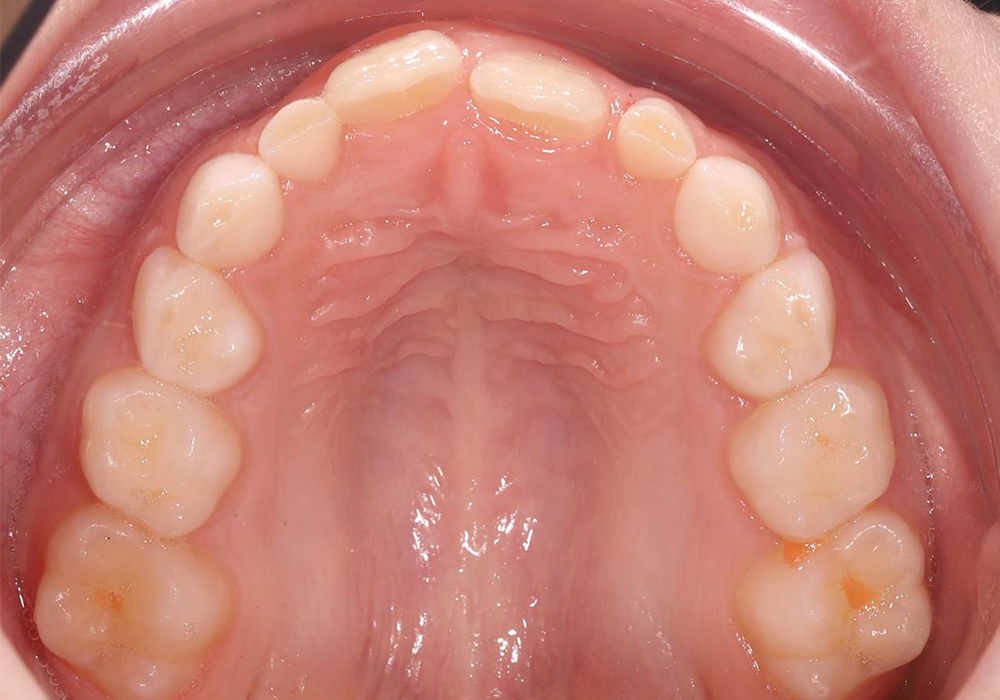

Создание условий для правильного прорезывания постоянных зубов при сужении зубных рядов у ребёнка